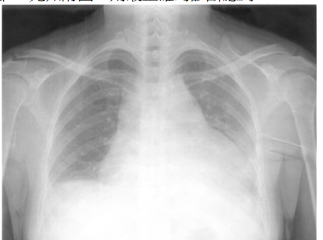

33 一位 28 歲女性最近半年來臉頰部有紅斑(如附圖)及手指、手腕和肩膀有偶發性疼痛。曾經被醫師懷疑為紅斑性狼瘡。請問下列那些檢查對疾病的診斷最有幫助?

① skin biopsy ② anti-nuclear antibodies ③serum complements C3 and C4 level ④rheumatoid factors ⑤complete blood routine ⑥ anti-dsDNA antibodies ⑦ anti-SS-A/anti-SS-B ⑧ serum electrophoresis ⑨ LE test(A)①④⑧(B)③⑦⑨(C)②③⑥(D)④⑤⑦